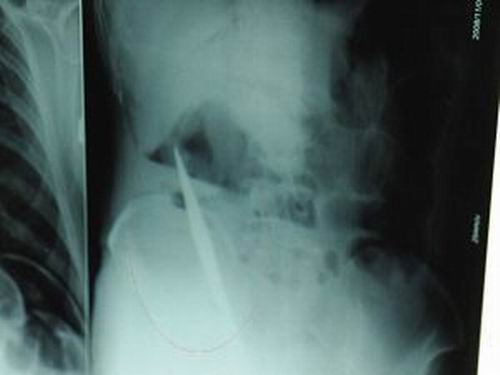

X光片上,尖刀清晰可見。

從男子體內取出的尖刀足足有19厘米長。

江蘇銅山一58歲男子因服毒被送到醫院搶救,可醫生采取搶救措施后卻發現效果不佳。后來經細致檢查,醫生有了個驚人的發現,該男子的體內竟然有一把尖刀,醫生通過手術將位于其腹部右側橫結腸下緣的尖刀取了出來。這把尖刀足足有19厘米長!據醫生推測,這把刀應該是從肛門推進體內的,不知男子為何想以如此殘酷的方式結束自己生命。由于搶救及時,該男子已暫時脫離危險。

昨天(11月6日)上午,記者在徐州礦務集團總醫院重癥監護室見到了這名男子,目前他雖然已經恢復了意識,但還不能開口說話,需要呼吸機輔助呼吸。據醫生介紹,4日中午12時左右,這名男子因服毒輕生被緊急送到醫院進行搶救,之前,這名男子已經在當地鄉鎮醫院進行了近20小時的治療,但效果不佳。“病人被轉院到礦總院時已神志不清,血壓極低,處于休克狀態。”救護人員給男子洗胃、初步處理以后,發現男子呼吸急促,于是趕緊給他拍片檢查。結果讓所有的醫生大吃一驚,竟有一把尖狀異物橫在該男子腹腔內!當天下午5時30分,輕生男子被推上了手術臺。經過40多分鐘的手術,該男子腹腔被打開,手術醫生發現,男子體內的金屬狀異物竟然是一把長19厘米的尖刀!

醫生告訴記者,手術后,醫生在病人身上并未發現刀痕,最后,經過檢查發現,在該男子直腸處找到穿孔。醫生從醫學角度分析后認為,這把尖刀應該是從肛門插入直腸的。